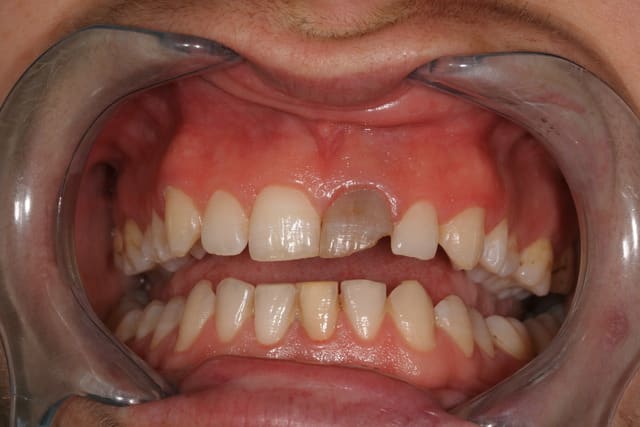

Tu peux faire une gouttière unitaire et utiliser du peroxyde de carbamide à 15% (et pas acid) en port nocturne.

Exemple d'un cas.

Img 9016 vmveq2 - Eugenol

Img 9020 hbsntd - Eugenol

Img 9022 fnap0p - Eugenol

Img 9132 emw9hu - Eugenol